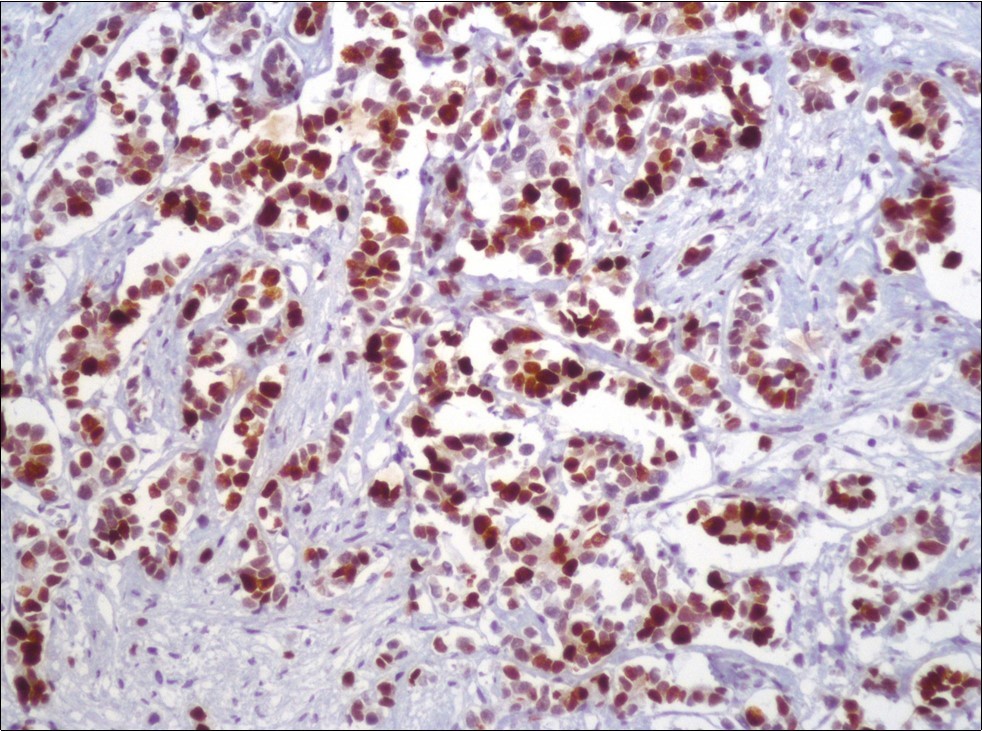

A 73-year-old male patient was admitted to our outpatient clinic with acute urinary retention. Digital rectal examination was normal. The PSA value was 1.81 ng/dl. Prostate size was 101 cc. Since the PSA value and digital rectal examination were normal, no biopsy was taken. Ultrasonography showed bilaterally ureterohydronephrosis. The creatinine level was 2.89 mg/dl. Hypertension has been presented as a comorbidity. An 18 Fr Foley catheter was inserted and alpha-blockers and 5-α reductase inhibitor medication was given. Creatinine level decreased to 0.91 mg/dl after one week. When the patient's catheter was pulled out, he could not urinate again. A catheter was inserted and waited one week more. After one week, the patient was unable to urinate again. The operation was decided due to this recurrent urinary retention. Because of prostate size was 101 cc and prostatic urethra was long, open prostatectomy was decided. When the prostate was removed during the operation, it was evaluated that the left side and the lower side were adhered to surrounding tissue. The prostate was removed as an en bloc. The catheter was removed after 5 days. The pathology of the patient has been reported as pure small cell prostate carcinoma. On the microscopic examination, the tumor was heavily infiltrated into the prostate parenchyma (Figure 1). Tumor cells were consist of atypical small-medium sized, mitotically active cells with a high nuclear to cytoplasmic ratio, hyperchromatic nucleus, nuclear molding, and inconspicuous nucleoli (Figure 2). On the immunohistochemically examination of synaptophysin showed diffusely and strong positivity while chromogranin A showed focal weak positivity with the absence of staining for PSA (Figure 3). Ki67 proliferative index was equal to 90% of the tumor cells (Figure 4). The results confirmed the diagnosis of prostatic small cell carcinoma. Metastatic lymph nodes were detected in the right perirectal region with metastatic multiple lymph nodes in the bilateral external iliac region, more on the left than in the PET CT. No metastasis was detected in the brain MRI and thorax computed tomography. Four cycles of etoposide and cisplatin chemotherapy were administered to the patient. Control PET CT taken after chemotherapy showed a significant decrease in size and metabolic activity of the right obturator and lymph nodes in the right perirectal area. The size and metabolic character of the left obturator, left external iliac and common iliac lymph nodes were increased. After a month, patient admitted to emergency outpatient clinic with left flank pain. There was an 8-cm mass in retroperitoneal area in the computed tomography. Supportive treatment was started because the patient could not tolerate chemotherapy. The masses reached to 13x11cm and fulfilled the retroperitoneal area. Multiple lung metastases were seen. The patient died 13 months later after the first diagnosis.

Figure 2.The tumor cells show rosette formation with hyperchromatic nuclei and nuclear molding (H&E, x200)